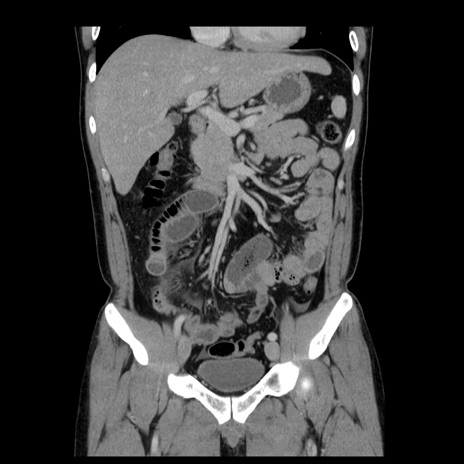

症例4(冠状断像)

【症例】30歳代男性

【主訴】腹痛、嘔吐

【現病歴】昨晩から突然の腹痛あり、その後嘔吐、軟便も出現。腹痛が改善しないため救急搬送となる。2日前にしめ鯖の食事歴あり。

【身体所見】意識清明、苦悶様、BP 135/90mmHg、BT 35.7℃、腹部:平坦、やや硬、心窩部〜臍部に自発痛、圧痛あり、筋性防御+、反跳痛-

【データ】WBC 8100、CRP 0.57